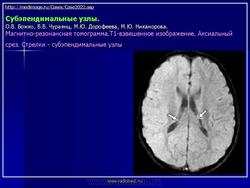

На поверхности мозга наблюдаются единичные или множественные глиома-тозные узлы, по цвету несколько светлее окружающего мозга и плотнее его на ошупь, возможна их кальцификация. Узлы могут быть и в белом веществе, под­корковых ганглиях, а также в стволе мозга и в мозжечке.

Встречаются и аномалии развития извилин мозга в виде микро- и пахигирии. Заболевание чаще носит спорадический характер. Бляшки достигают диаметра 5-20 мм. В коре больших полушарий и мозжечка иногда могут быть обнару­жены пластинчатые тельца, напоминающие амилоид. Происходит дегенерация клеток коры. При КТ-исследовании головы нередко можно выявить кальцифика-ты и глиальные узелки в паравентрикулярной области, субэпендимарно вдоль на­ружных стенок боковых желудочков, в зоне межжелудочкового отверстия Мон­ро, реже - в мозговой паренхиме. На М РТ головного мозга в 60% выявляются гипотеденсивные очаги в одной или обеих затылочных долях, которые расце­ниваются как участки неправильной миелинизации (Козлов А.В., 2002).